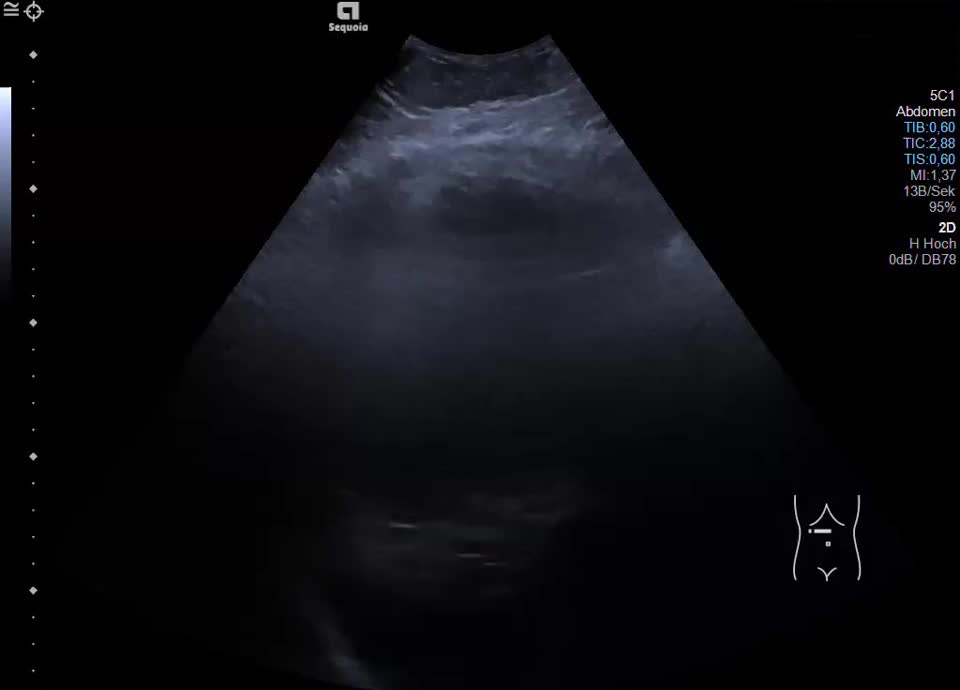

Leberhämatom (HELLP-Syndrom)

Kasuistik: die 48-jährige Patientin hat während ihrer Schwangerschaft ein HELLP-Syndrom entwickelt. Zustand nach Sectio bei schwerer Präeklampsie und Gemini in der 37. SSW. Post-partales HELLP mit Leberhämatom und beginnendem Leber- und Nierenversagen. Durch die Interventionelle Radiologie erfolgte die CT-gestütze Embolisation mit Coils. Sonographisch stellt sich jetzt ein 12x13cm messendes subkapsuläres Hämatom im rechten Leperlappen mit Anzeichen einer beginnenden Organisation dar. Die Läsion nimmt kein Kontrastmittel auf, eine aktive Blutung kann ausgeschlosen werden.